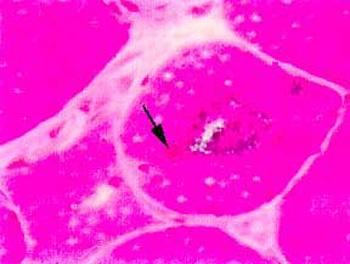

The diagnosis of inclusion body myositis is suspected in the presence of the history and examination compatible with a chronic acquired muscle disease. Once the diagnosis is suspected, the initial diagnostic steps include obtaining blood for CPK level and a muscle biopsy. The muscle biopsy of inclusion body myositis shows mild to moderate inflammation, atrophic denervated fibers, and most characteristically "rimmed vacuoles" as well as some muscle fibers with eosinophilic inclusions. Abnormal deposits of a substance called amyloid can be demonstrated upon histologic examination in and around the vacuoles and inclusions.